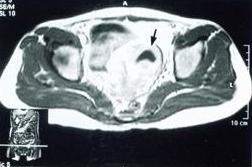

宮角妊娠透視觀察血管性介人治療套用於宮角妊娠的病例較少,其治療方法與宮頸妊娠相似。

宮角妊娠側面透視血管性介入治療

血管性介人治療套用於宮角妊娠的病例較少,其治療方法與宮頸妊娠相似。